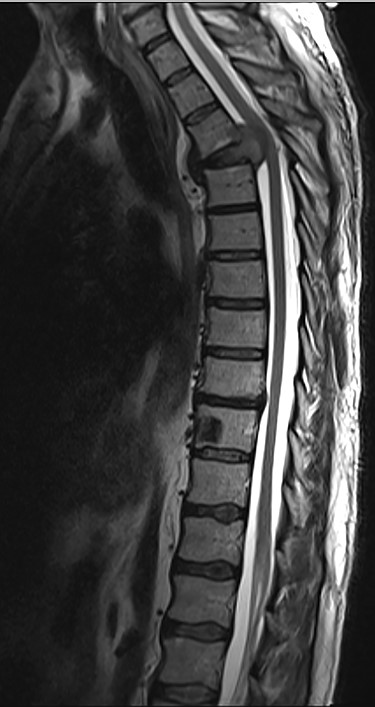

Spinal images are presented in Figs 1–6. Cross-sectional imaging revealed no other neoplastic lesion. He received dexamethasone 10 mg bolus then 4mg four times daily with appropriate proton pump inhibitor coverage. Due to no distinguishable major arterial feeder upon review of the imaging jointly with the neuroradiologist, pre-operative embolization was not attempted. The following morning, he underwent posterolateral right costotransversectomy, ligation of the ipsilateral T4 nerve root, T4 vertebrectomy and insertion of an expandable titanium cage with T1–T7 pedicle screw fixation (Figs 7 and 8). Post-operatively his pain improved to VAS 2/10 and motor power in his left lower limb improved to MRC grade 4/5. The patient was discharged home Day 10 post-admission with physiotherapy.

Sagittal T2-weighted magnetic resonance image (T2W MRI) with T4 metastatic epidural spinal cord compression (MESCC) and a synchronous T10 lytic lesion.

Sagottal T2W MRI showing synchronous lytic lesions in T10 & L3 vertebral bodies.